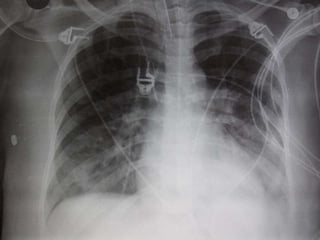

 Diffuse infiltrates

 CXR – diffuse alveolar infiltrates

 Severe endof the spectrum of acute lung injury  Acute and persistent lung inflammation with increased vascular permeability  Diffuse infiltrates  Hypoxemia – paO2/FiO2 <200  (i.e. pO2 70 / FiO2 0.5 = 140)  No clinical evidence of elevated left atrial pressure (PCWP <18 if measured)

 Early  Incitingevent, pulmonary dysfunction (worsening tachypnea, dyspnea, hypoxemia)  Nonspecific labs  CXR – diffuse alveolar infiltrates  Subsequent  Improvement in oxygenation  Continued ventilator dependence  Complications  Large dead space, high minute ventilation requirement  Organization and fibrosis in proliferative phase